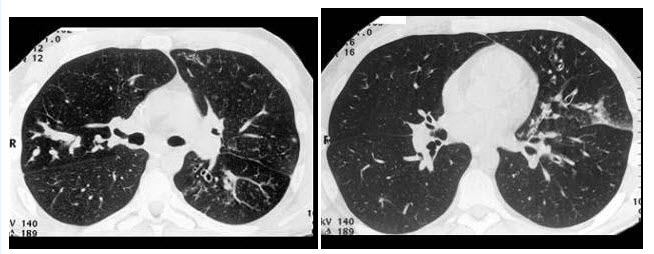

C.原发性肝癌

D.肝血管瘤